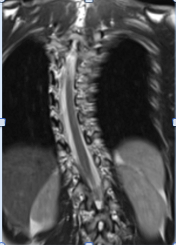

حالة رقم 18084. يبين الرنين المغناطيسي كيف يلتصق الحبل الشوكي بالجزء الداخلي من العمود الفقري